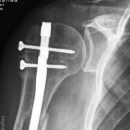

Dislozierte subcapitale Fraktur mit Tbc majus

Subcapitale Fraktur und Tuberculum majus